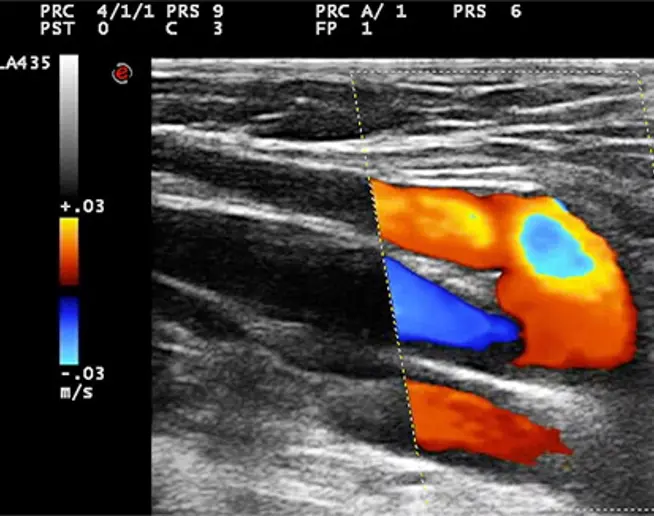

A century later Claude Franceschi took over the hemodynamic approach and developed complementary concepts thanks to the Doppler Ultrasound vascular investigation he pioneered and published in the very first book in 1977 as well as the first vascular Ultrasound imaging book in 1986. He studied fluid mechanics to understand his observations, then he proposed a hemodynamic model of venous pathophysiology.

The acronym C.H.I.V.A. stands for “cure Conservatrice et Hemodynamique de l’Insuffisance Veineuse en Ambulatoire": conservative and hemodynamic treatment of venous insufficiency in out-patients. This treatment was proposed by Claude Franceschi in October 1988 at a scientific meeting in Précys-sous- Thil. It represents a therapeutic approach to treating Chronic Venous Insufficiency (CVI) of the lower limbs in outpatients, with a focus on preserving the venous system and the Great Saphenous Vein (GSV) while ensuring the restoration of tissue drainage. (scegliere foto)